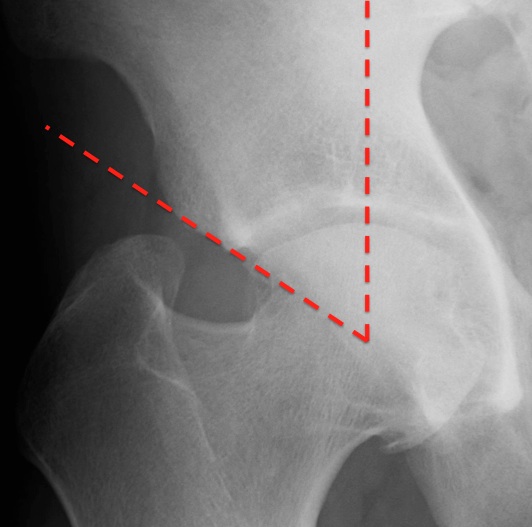

angle formed by a vertical line and a line connecting the femoral head center with the lateral edge of the acetabulum. compare normal (figure 1) with abnormal over coverage (figure 2)

ABNORMAL:

if < 25 degrees then dysplasia

if > 39 degrees then acetabular over coverage, seen in pincer type femoral acetabular impingement

how to draw the center edge angle